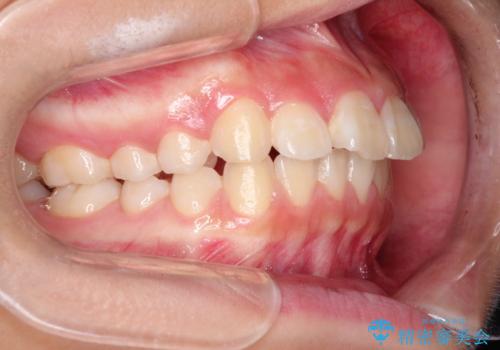

- 前歯が出ているのを主訴に来院されました。

上の前歯が前方に傾斜しており、上の前歯と下の前歯が接触していない状態でした。

上の奥歯を後方に移動させて、前歯を引っ込める計画としました。

しっかり使っていただけたので、スムーズに治療を終了することができました。